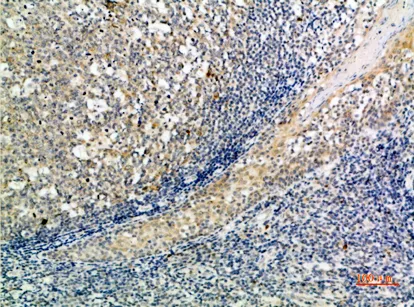

CD1A/B Rabbit Polyclonal Antibody($99/20μL)

Cat: APRab08259

Size1:20μL Price1:$99

Size2:50μL Price1:$118

Size3:100μL Price2:$220

Size4:200μL Price3:$380

Application:IHC-P,IF-P,IF-F,ICC/IF,ELISA

Reactivity:Human,Rat,Mouse

Conjugate:Unconjugated

Optional conjugates: Biotin, FITC (free of charge). See other 26 conjugates.

Gene Name:CD1A CD1B